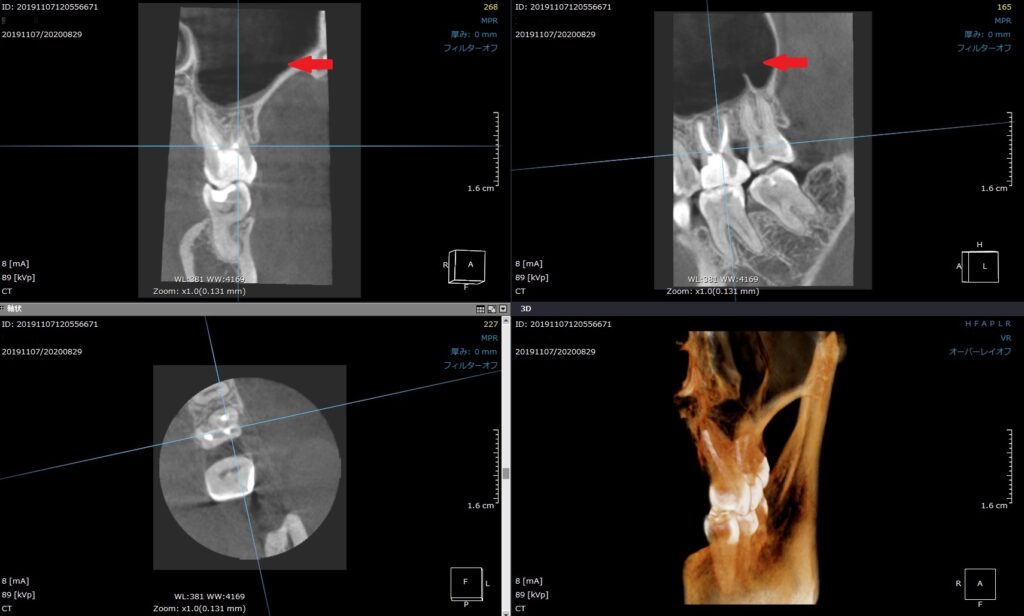

治療して10カ月後のCT写真です。

赤い矢印の位置の灰色が無くなりました。

ここは本来、空洞で空気があるために、CT画像では黒く抜けて写ります。

横からの画像。(左:治療前 右:治療後)

右が治療10か月後。神経を取ってお薬を入れたので、

根に向かって白いスジが見えます。

膿の袋が無くなっています。